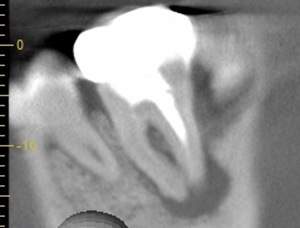

| 根の中にお薬を充填した後のCT画像。やはり根の先に黒い影があるのがわかります。 |

| 根の先の黒い影は消失しました。 | 術後6ヶ月のCT画像です。こちらでも、根の先に黒い影は見当たらないです。 |